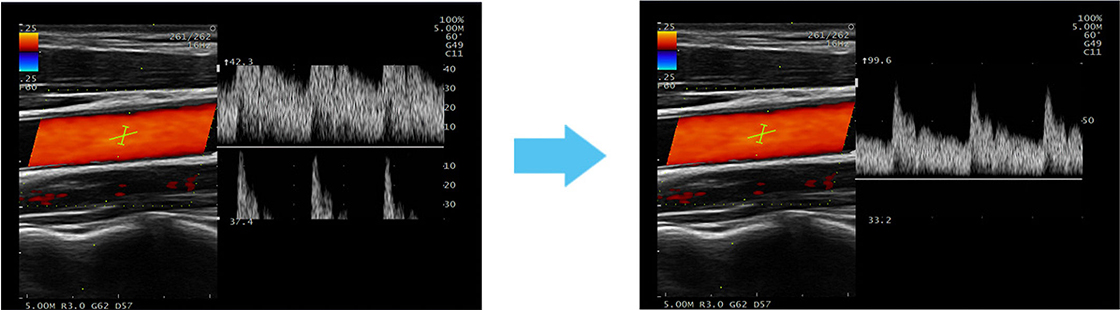

Las imágenes se pueden ajustar al presionar un botón una sola vez: Se optimizan la ganancia del modo B, la posición inicial y el rango de velocidad de la forma de onda Doppler.

[izquierda] Antes del ajuste de la forma de onda de PW

[derecha] Después del ajuste de la forma de onda de PW